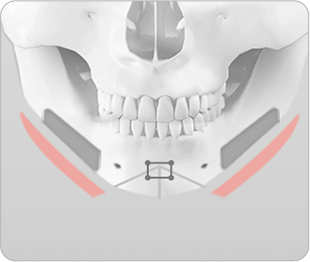

브라운의 ㅅ절골술 이용한 앞턱 수술

ㅅ절골술은 턱끝의 길이를 조절하여 길게 하거나 짧게 줄일 수 있으며, 무턱이나 주걱턱을 보형물이나 뼈 이식 없이 효과적으로 개선할 수 있습니다. 또한 동시에 비대칭이 심하거나 넓은 턱끝도 부드러운 V라인 턱끝을 만들 수 있으며, 턱끝 신경과 치아뿌리를 피해 절골하기 때문에 신경과 치아 손상없이 안전하게 수술할 수 있습니다.

턱끝이 넓은 경우

ㅅ절골술 진행 시 턱끝 중앙뼈를 2~10mm 까지 다양하게 절제하여 턱끝의 넓이를 조절할 수 있습니다.